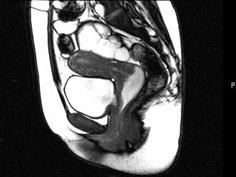

问题 女,28岁,阴道有异常液体流下,CT和MRI扫描如图,下列说诊断正确的是 ( )

选项 A、考虑为左侧输尿管异位开口 B、考虑为膀胱阴道瘘 C、MRI的T2加权像示宫颈阴道内有大片状高信号影 D、膀胱后下缘可见鸟嘴状突起 E、CT增强示造影剂由膀胱进入阴道

答案 BCDE